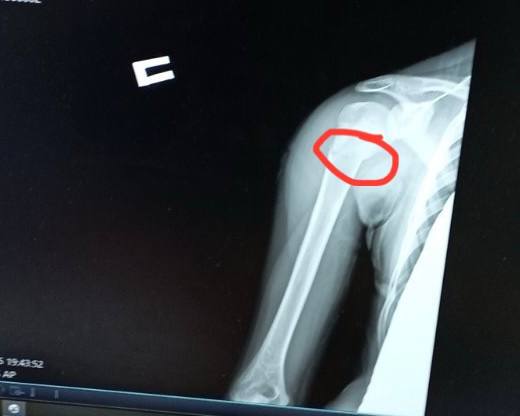

Дворічний Даніель отримав важку травму вдома – бігав, упав. Як наслідок – косий перелом стегнової кістки, складний для вправлення та лікування, утримання відламків.Ортопед-траматолог Ігор Тарасюк пояснює: «Лікування гіпсовими пов’язками хлопчику не підходить, тож раніше діти з такими травмами лікувалися впродовж місяця на витяжінні, а після цього застосовували кокситну гіпсову пов’язку, яка утруднювала рухи. Завдяки внутрішньокістковій фіксації еластичними титановими стержнями дитину виписуємо додому вже наступного дня. Хлопчик, хоч і з певними обмеженнями, але вже може самостійно рухатися».Ще одна пацієнтка відділення — 11-річна футболістка Юля, яка невдало впала на плече під час гри. Як наслідок – перелом плечової кістки зі зміщенням. Раніше через такий перелом довелося б носити велику гіпсову пов’язку на руці – від кисті до плеча, також гіпс накладали б для фіксації і на обидва плеча.Після операції через два-три дні дівчинка вже вільно рухає рукою, не відчуває обмежень. На руці залишиться лише невеликий шрам у 2-3 сантиметри. Через кілька тижнів дівчинка зможе повернутися до занять футболом.Читати ще: Арахіс у легенях, магніти в стравоході та опіки від побутової хімії: волинські лікарі розповіли, із чим до них привозять маленьких пацієнтів